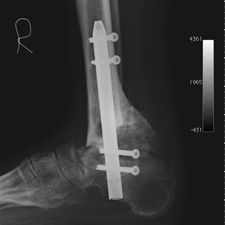

He opted to have a right hind foot arthrodesis, which was carried out utilizing an intramedullary arthrodesis nail, which was performed in July 2011.

He has gone onto have good healing and fusion of the ankle with preservation of his foot and has allowed him to mobilize independently without pain and return to his job. At last review he was independently mobilizing and did not have any pain, He has restarted working and has no problems.